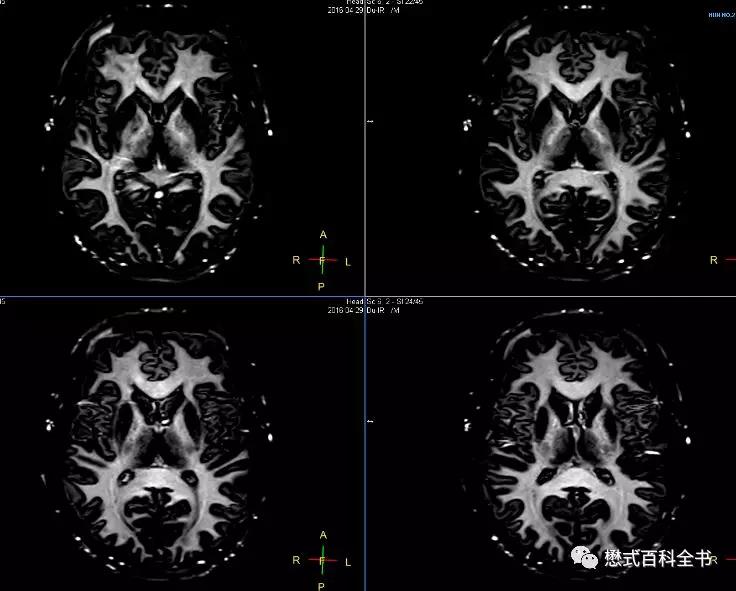

大家记住了这些参数后,自己在自家医院的MR设备上,都可以调出来。细心的老师还发现,虽然这个序列叫双反转,其实无论是脑灰质成像,还是脑白质成像,脂肪信号都被抑制掉了,可以先采用SPIR进行脂肪抑制。这样算下来的话,这个序列其实是一个准三反转序列(虽然SPIR反转的不是180°)。在血管壁或者心脏扫描中,为了彻底的抑制血液信号,也会采用双反转序列来达到黑血成像的目的。如果在黑血成像的基础上再进行脂肪抑制,则还需要提前施加一个反转脉冲对脂肪组织进行抑制,这样就组成了三反转序列。

前文链接:磁共振黑血成像技术(Black Blood)

双反转序列可以结合不同对比度的图像,比如T1WI、T2WI、PDW等。